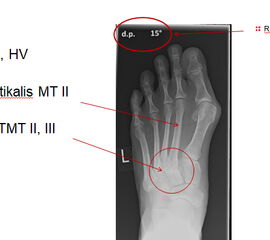

Bei nicht traumatischen Arthrosen am Tarsometatarsale (TMT) II und III Gelenk handelt es sich meist um proximale Überlastungsschäden bei ausgeprägtem Spreizfuß mit Instabilität im TMT I Gelenk oder auch alleiniger Hypermobilität im TMT I und dadurch fehlender Lastaufnahme über den ersten Strahl.

Häufig werden die Arthrosen der Lisfranc-Gelenklinie relativ spät diagnostiziert. Die Gründe dafür liegen oft daran, dass die Patienten selbst einen Schmerz an der Fußwurzel nicht mit dem Symptomkomplex Spreizfuß und Hallux valgus in Verbindung bringen. Auch werden in der Primärdiagnostik häufig nur vom Vorfuß Röntgenbilder angefertigt oder die angewandte Röntgentechnik erlaubt keine Einsicht in die Lisfranc-Gelenklinie.

Eine Röntgenaufnahme unter Belastung mit Abbildungen des ganzen Fußes a. p. (mit 15-20° Röhrenkippung) und seitlich, sowie Schrägaufnahmen, reichen meist zur Diagnose. Manchmal ist ein MRT und DVT ergänzend hilfreich. Selten wird die Indikation für ein SPECT CT gestellt (Abb. 6).

• konventionelle Röntgenbilder mit Belastung im Stehen a. p. und seitlich, ggf. schräg (Abb. 9, 10 und 11).